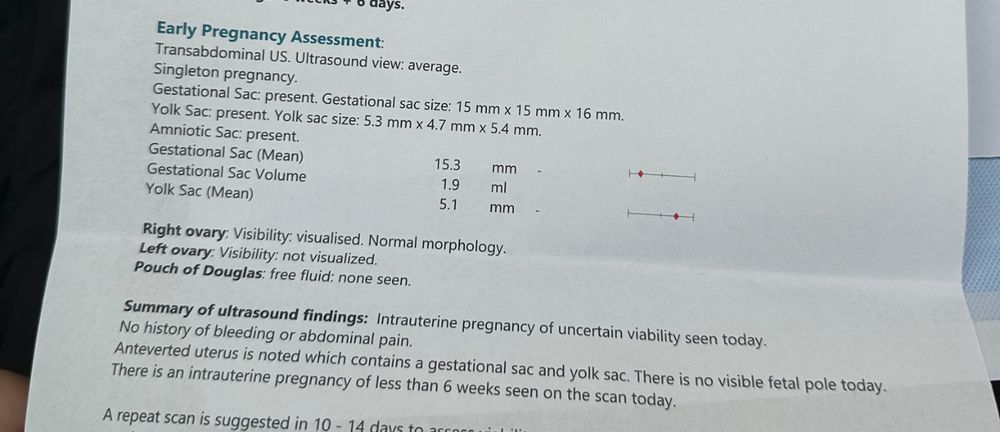

Здравствуйте девочки - вопрос возможно глупый но ситуация странная. Итак, в прошлую субботу мне исполнилось 3 недели после 5-дневного переноса эмбрионов. Итак, сканирование показало эмбрион размером 1,9 мм и плодное яйцо диаметром 9,5 мм. Я сдавала ХГЧ 4 раза за этот период и все в порядке. Вчера сделала сканирование (то есть через 4 недели после переноса) и уже виден только мешок 15,3 мм, а эмбрион исчез? Может ли быть такое - одну неделю эмбрион существует, а вторую неделю чудесным образом исчезает? У меня не было ни кровотечения, ни болей в животе. Прикрепляю фото первого скана с эмбрионом и второго вчерашнего скана без эмбриона. Врач рекомендовал мне продолжить лечение до следующего четверга и сделать еще одно сканирование через 5 недель после переноса. Любые предложения и советы будут оценены по достоинству. Большое спасибо

это и скан и анализ крови в один день

это и скан и анализ крови в один день